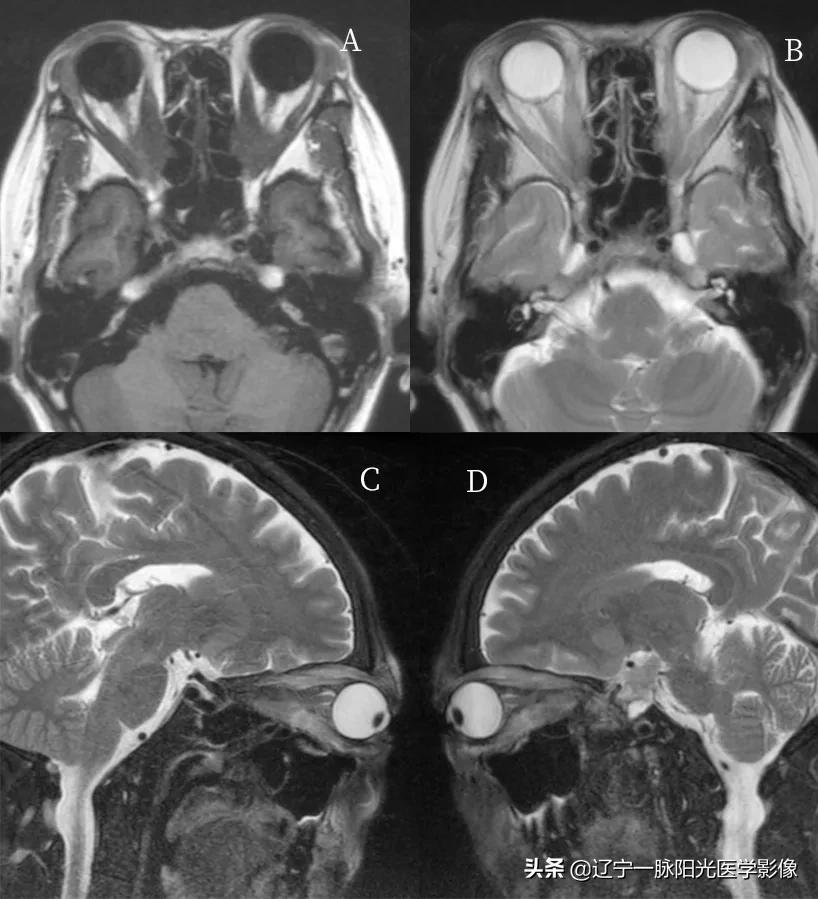

简要病史:女,59 岁,甲状腺功能亢进 5 年,双眼突出半年余

图 A、B、C、D 轴位、冠状位及矢状位示双侧眼球对称性突出,眼肌均匀增厚,以上、下直肌明显,球后脂肪减少

图 A、C、D 双侧球内玻璃体、晶状体密度正常。视神经走行正常,密度均匀,边界清楚

影像学一般依靠 CT、MRI 检查,诊断依据为眼外肌肌腹增粗而附着于眼球壁的肌腱不增粗,而且常是双侧下直肌、上直肌、内直肌肌腹增粗